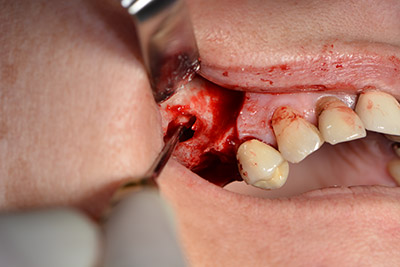

Die anschließenden Bohrungen werden mit einer reduzierten Umdrehungszahl von 300/min durchgeführt. Hier zeigt sich einer der Vorteile der Implantmed. Das chirurgische Protokoll kann voreingestellt werden – die einzelnen Positionen sind über einen einfachen Druck auf die Position „P“ der Fußsteuerung anwählbar. (Abb. 10 bis 11)

Die nächste programmierte Position ist bereits die Implantateinbringung und in unserem Hause mit einer Kraft von 32 Ncm voreingestellt (Abb. 12).